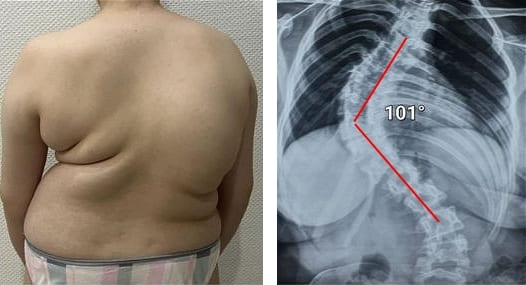

Mire estas fotografías. Esto es lo que les sucedió a todos los que ignoraron los síntomas. Hoy, estas personas están completamente sin esperanza, y muchos de ellos no tienen a quién acudir en busca de ayuda. ¿Realmente, quiere un destino así?

"Joroba de viuda" — deformación de las vértebras y dolor crónico, insoportable, que se intensifica cada día.

Una de las pocas soluciones que puede ofrecer la ciencia médica es una cirugía complicada y riesgosa para extirpar la hernia e instalar clavijas metálicas. ¡Pero, piénselo! Incluso los mejores cirujanos reconocen que la cirugía de columna es una medida extremadamente inapropiada y peligrosa, QUE A MENUDO CONDUCE A PROBLEMAS MÁS GRAVES, INFECCIONES, CONTAGIOS, COMPLICACIONES E INCLUSO A LA MUERTE.

La extracción de una hernia de columna con clavijas metálicas es un procedimiento que, a menudo, puede causar muchas complicaciones: el riesgo de infección, amputación o septicemia aumenta en un 60%. El proceso de recuperación es largo y doloroso, con un riesgo significativo de discapacidad.